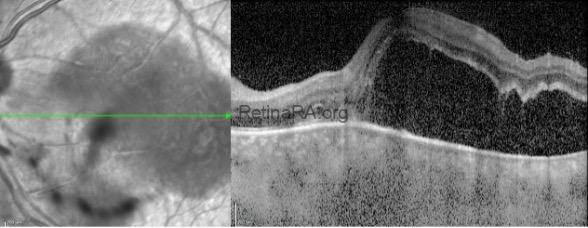

OCT showed intravitreal hyperreflective spots concentrated on the lesion, full-thickness retinal involvement, and serous retinal detachment.

With the diagnosis of ocular toxoplasmosis, trimethoprim sulfamethoxazole with azithromycin and oral steroid treatments were started. In the 1st month control OCT imaging, scarring in the lesion and complete recovery of serous detachment were observed.